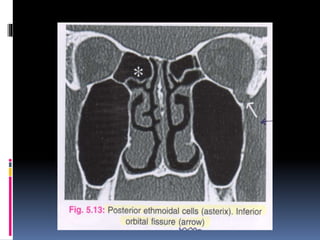

 The posterior ethmoidal cells are larger and fewer

than the anterior ethmoidal cells.

 The fissure between the orbit and the

maxillary sinus i.e. the INFERIOR ORBITAL

FISSURE is seen in this cut.

 The INFERIOR ORBITAL FISSURE opens into

the INFRATEMPORAL FOSSA